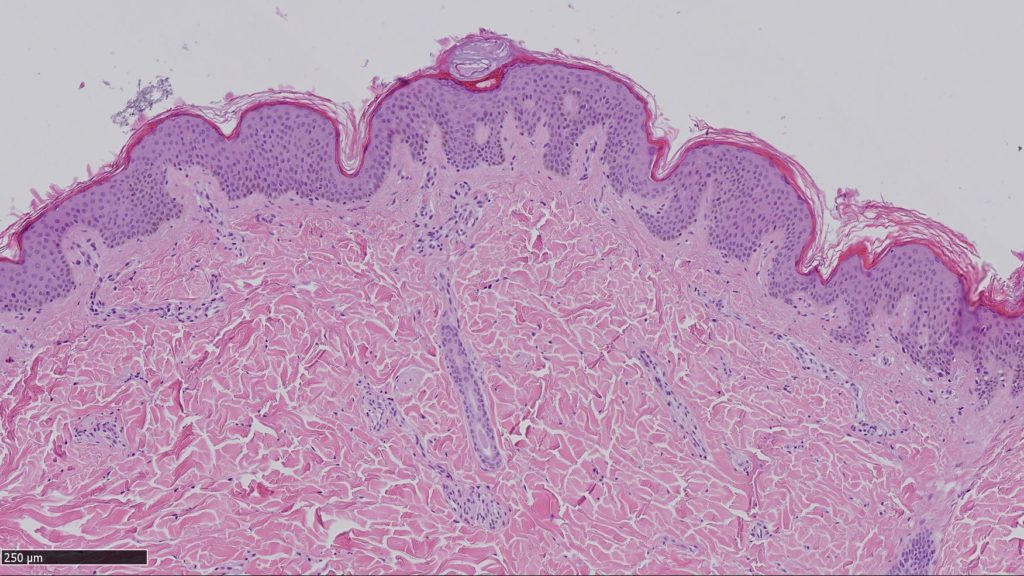

A Sassari, nella struttura di Anatomia Patologica nel 2018 sono stati diagnosticati 67 melanomi infiltranti, quando cioè la membrana basale dell’epidermide è superata ed è infiltrato il derma a vari livelli di profondità, e 30 in situ, cioè melanomi non invasivi contenuti nella membrana basale dell’epidermide. Dai dati a disposizione della struttura sassarese, la sopravvivenza a 5 anni è descritta con un range variabile nelle diverse realtà dal 75 per cento a circa il 90 per cento.